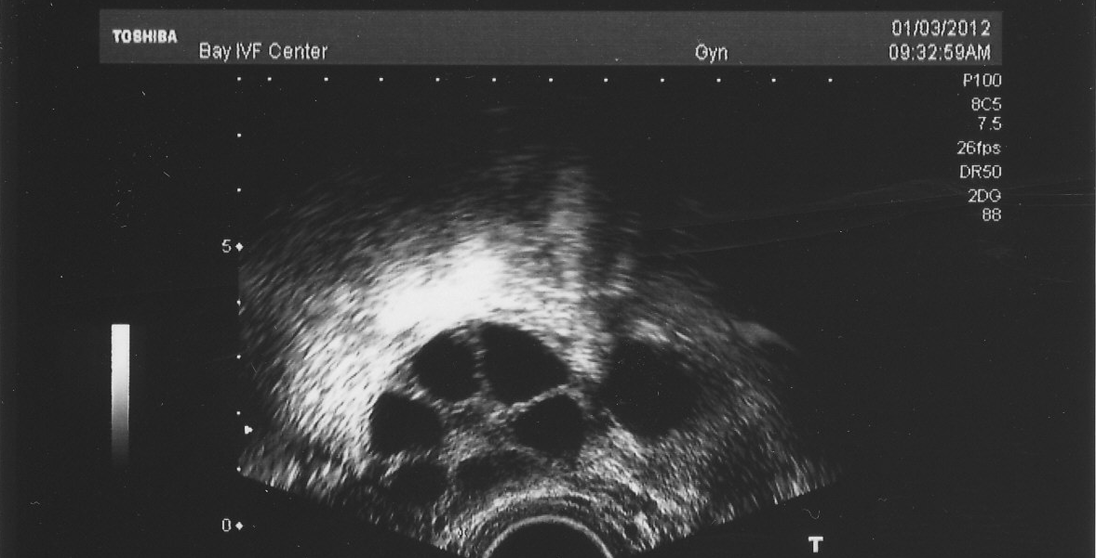

Why Follicles Matter in IVF

So, why all the fuss about follicles? In IVF, they’re the stars of the show. The more follicles you grow, the more eggs you might get, and the better your shot at a successful pregnancy. Doctors use ultrasound to peek inside your ovaries and count these little sacs—specifically the ones called “antral follicles,” which are big enough to see (about 2-10 mm). This count gives them a sneak peek at your “ovarian reserve”—aka how many eggs you’ve got left in the tank.

- Antral Follicle Count (AFC): This is the number of visible follicles (2-10 mm) at the start of your cycle. A “normal” AFC is usually 6-10 per ovary, so 12-20 total. Less than 6 might mean a low reserve, while over 12 could signal a high reserve (or sometimes conditions like PCOS).

- During Stimulation: Once you start IVF meds, doctors hope to see 8-15 follicles grow across both ovaries. Why not more? Too many (like 20+) can lead to a risky condition called Ovarian Hyperstimulation Syndrome (OHSS). Too few (under 4) might mean a canceled cycle.

| Start of Cycle (AFC) | 6-10 | 12-20 | Healthy ovarian reserve |

| Mid-Stimulation | 4-8 | 8-15 | Good response to meds |

| Ready for Retrieval | 2-5 mature | 4-10 mature | Enough eggs for a solid chance |